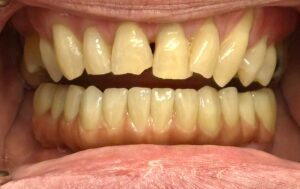

Full smile rehabilitation involving replacement of missing and failing teeth with implant-supported restorations, combined with aesthetic correction of existing dentition. The treatment was carefully planned to restore function, improve alignment, and achieve a balanced, natural-looking smile.

Implants were strategically placed to support long-term stability, with particular attention to soft tissue contours and emergence profiles to ensure seamless integration with the surrounding teeth. The final restoration was designed to enhance both aesthetics and bite function, delivering a confident and harmonious result.

This case demonstrates a comprehensive approach to implant and restorative dentistry, combining surgical precision with advanced prosthetic design to achieve predictable, long-term outcomes.